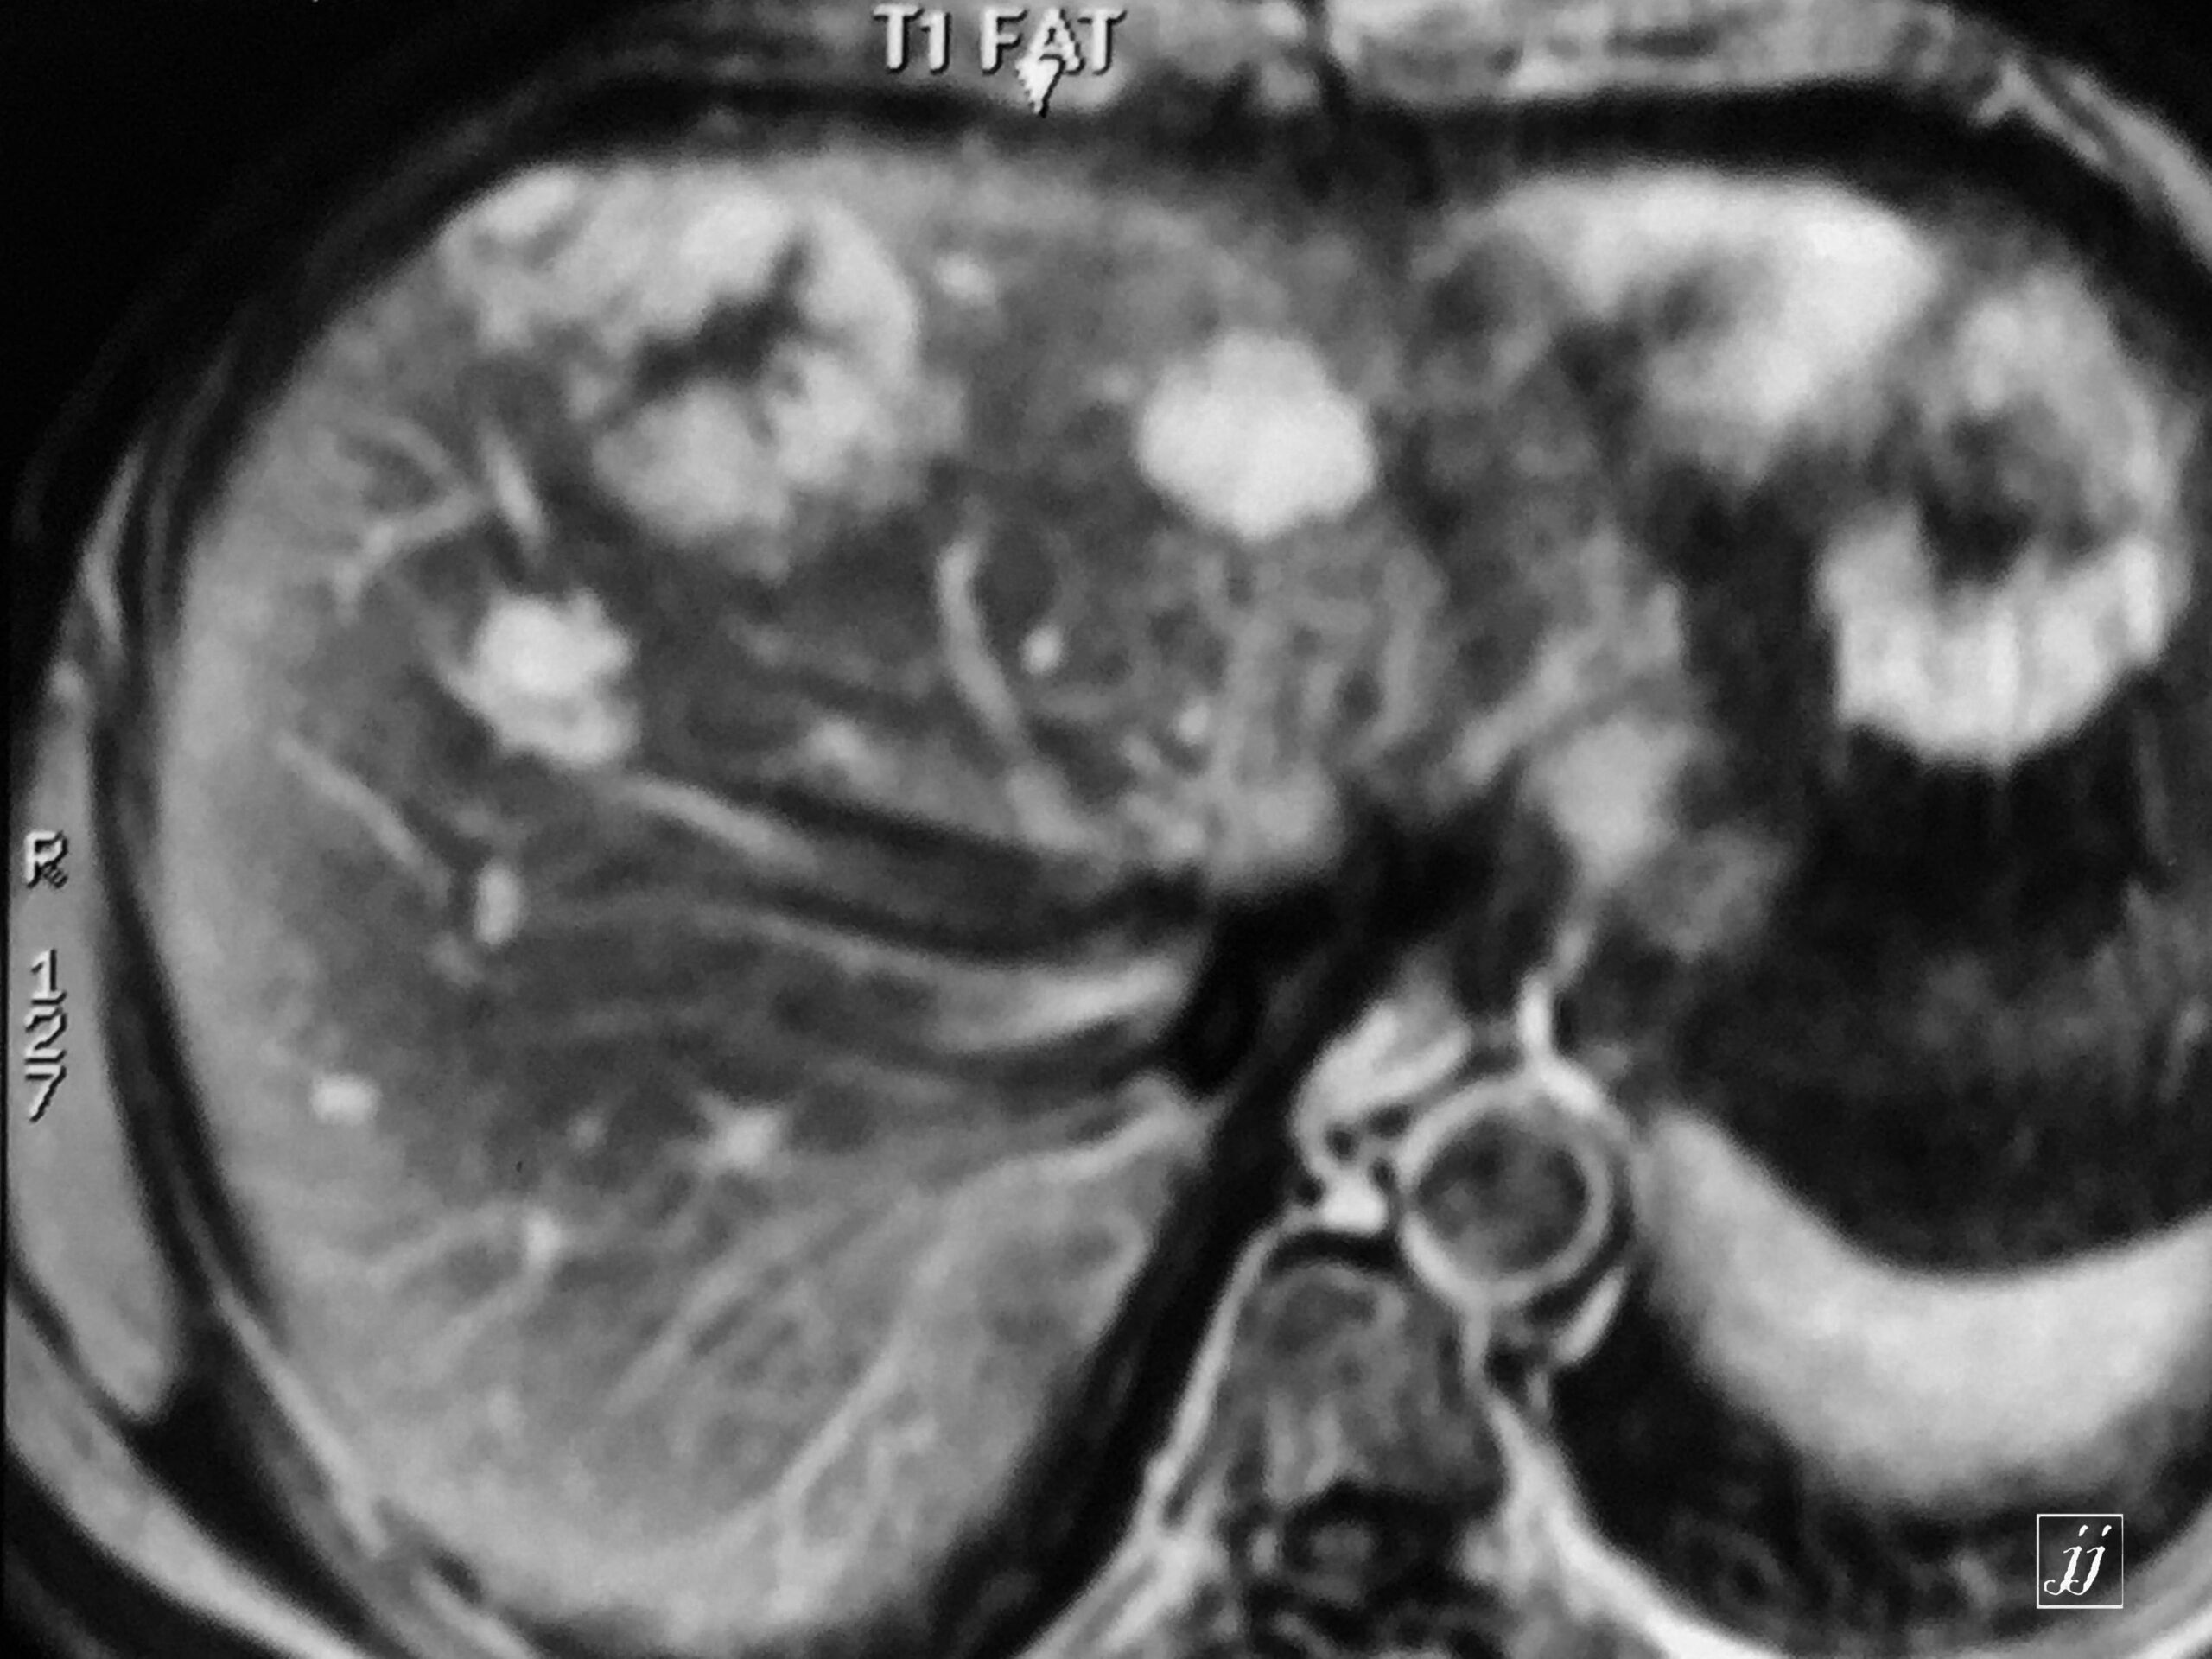

Abdomen- huge exophytic liver hemangioma with another two small hemangiomas (15)